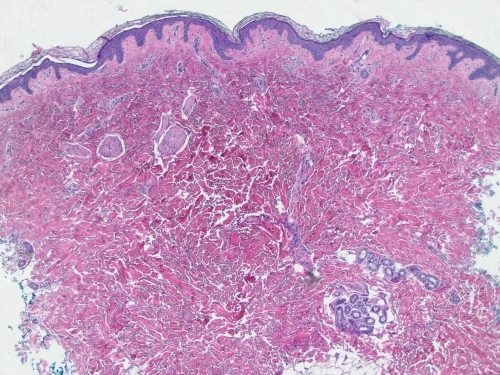

Ғылым тілінде невус деп те айтылатын бұл белгі сәби бойында ана жатырында жатқанында шығады екен. Адамның терісі екі қабаттан тұрады - ішкі және сыртқы. Эпидермис деп аталатын бірінші қабатында пигментация тудыратын меланоцит жасушалары синтезделеді екен. Баланың ана жатырында даму кезеңінде жасушалар ішкі теріден сыртқысына ауысады. Кейде бұл процес өз уақытында аяқталмай, меланоциттер ішкі теріде, яғни дермада қалып қояды. Осы пигмент тері бетіне қою көк түс береді. Бұл Моңғол таңбасы неден пайда болды деген сұраққа берілетін негізгі теория. Алайда нақты себебі әлі де зерттелмеген.

"Туа бітті невус тері меланомасына ұласады, алайда моңғол таңбасын гиперпигментацияның қатерлі аурулардың дамуына әкеп соғатын өзге түрлерінен ажырату маңызды. Дерматолог дифференциал диагностика өткізу мақсатында дерматоскоппия, сиаскопия немесе биопсия сараптамаларын тағайындайды", - дейді ол.